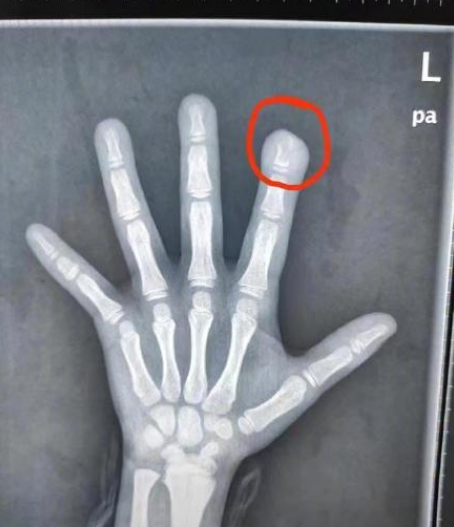

据文文(化名)的妈妈说,上周五孩子说自己食指疼,仔细一看,她的手指又红又肿,还有一个小洞,她忙带着女儿赶到武汉市第四医院就诊。 “送来时,孩子左手食指指尖破溃感染,还有脓性分泌物流出。”该院小儿骨科副主任医师徐剑说,文文食指指骨远节有骨质破坏,近1厘米长,是细菌侵蚀导致的,也是常说的骨髓炎。

原来,文文从4岁起就有咬指甲的习惯,十个指头的指甲都被她咬得坑坑洼洼,父母怎么劝说她都不听。上月,文文咬破了左手食指指尖,但一直没告诉家人,没想到导致严重感染。 针对文文的情况,目前彻底根治的方法就是“刮骨”,也就是将骨内局部感染的病灶彻底刮除。

术中,医生看到孩子左手食指指骨如同被虫蛀过一般,将感染的骨头彻底刮掉后,再用抗生素冲洗,最后将人工皮覆盖手指创面。术后,手指功能和外观将慢慢恢复正常。